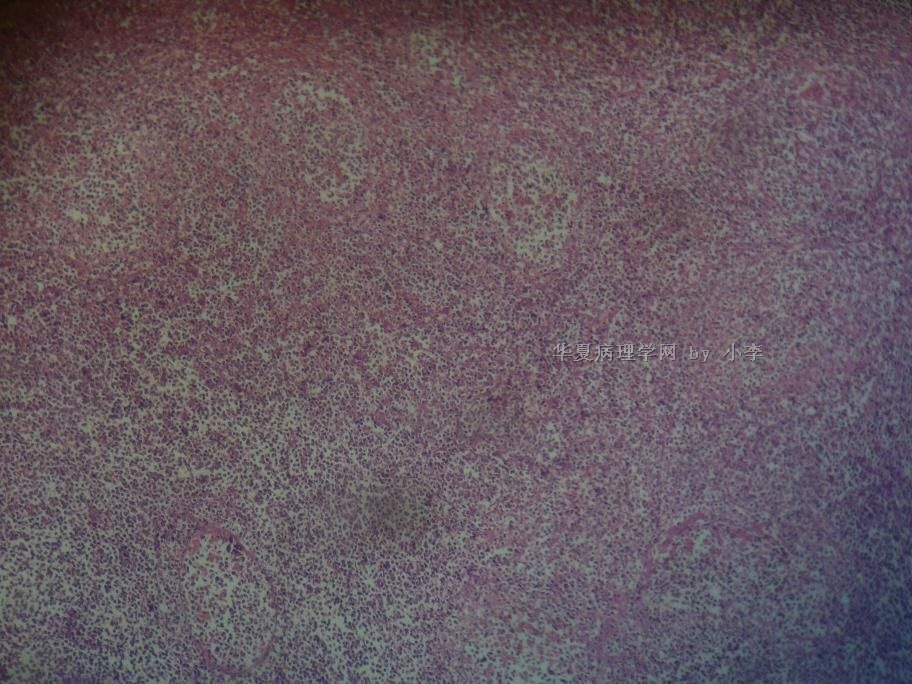

睾丸炎?

• 睾丸炎?图2

图2

首先考虑精子肉芽肿

肉芽肿性睾丸炎

精子肉芽肿